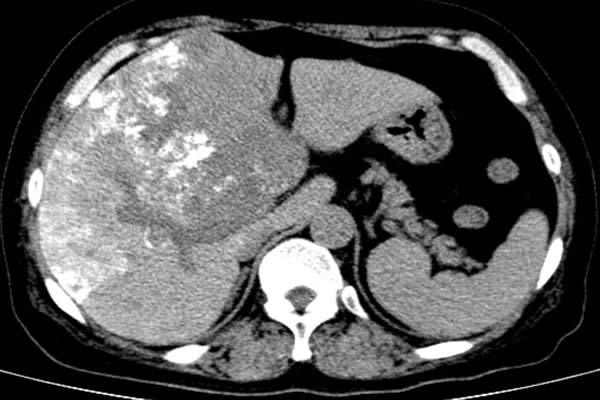

患者,女,62歲,以肝癌肝內(nèi)廣泛轉(zhuǎn)移收住入院,已無(wú)外科手術(shù)切除機(jī)會(huì),只能行介入化療栓塞術(shù)(TACE)。術(shù)中血管造影發(fā)現(xiàn)為肝臟供血的腹腔干已經(jīng)閉塞,導(dǎo)管無(wú)法進(jìn)入肝動(dòng)脈行介入化療栓塞術(shù),介入手術(shù)只能終止。由于已無(wú)其它治療方法,介入化療栓塞術(shù)終止,意味著患者只剩下1-2個(gè)月的生命??吹交颊吆图覍賹?duì)生命的渴望和對(duì)我們介入醫(yī)生的高度信任,我們不甘心就此放棄手術(shù)和延長(zhǎng)患者生命的機(jī)會(huì)。任小軍副主任反復(fù)研究血管造影圖像,見患者腸系膜上動(dòng)脈有側(cè)枝循環(huán)供應(yīng)到肝動(dòng)脈,仍有希望通過細(xì)小迂曲的側(cè)枝循環(huán)繞到肝動(dòng)脈進(jìn)行肝癌化療栓塞術(shù),但路途遙遠(yuǎn),操作復(fù)雜,手術(shù)時(shí)間長(zhǎng),醫(yī)生接受射線輻射大幅增加,并且成功的可能性很小,但是不嘗試,就沒有成功的機(jī)會(huì)。與家屬深入溝通后,任小軍副主任和任雪會(huì)副主任醫(yī)師反復(fù)耐心操作微導(dǎo)管,在技師和護(hù)士的高度配合下,導(dǎo)管終于成功進(jìn)入肝固有動(dòng)脈和肝右動(dòng)脈,對(duì)患者成功實(shí)施了介入化療栓塞術(shù),術(shù)后攝片和CT掃描顯示栓塞的碘油和化療藥大量沉積于肝臟腫瘤內(nèi),持續(xù)殺滅著腫瘤細(xì)胞?;颊咝g(shù)后反應(yīng)輕,恢復(fù)良好,現(xiàn)已出院。